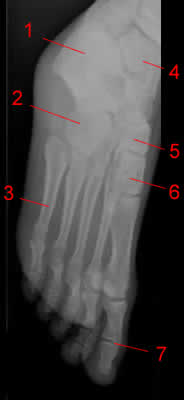

Стопа.

1, Малоберцовая кость.

2, Кубовидная кость.

3, Пятая плюсневая кость.

4, Берцовая кость.

5, Таранная кость.

6, Ладьевидная кость.

7, Cuneiform

8, Первая плюсневая кость

9, Проксимальная фаланга

10, Дистальная фаланга